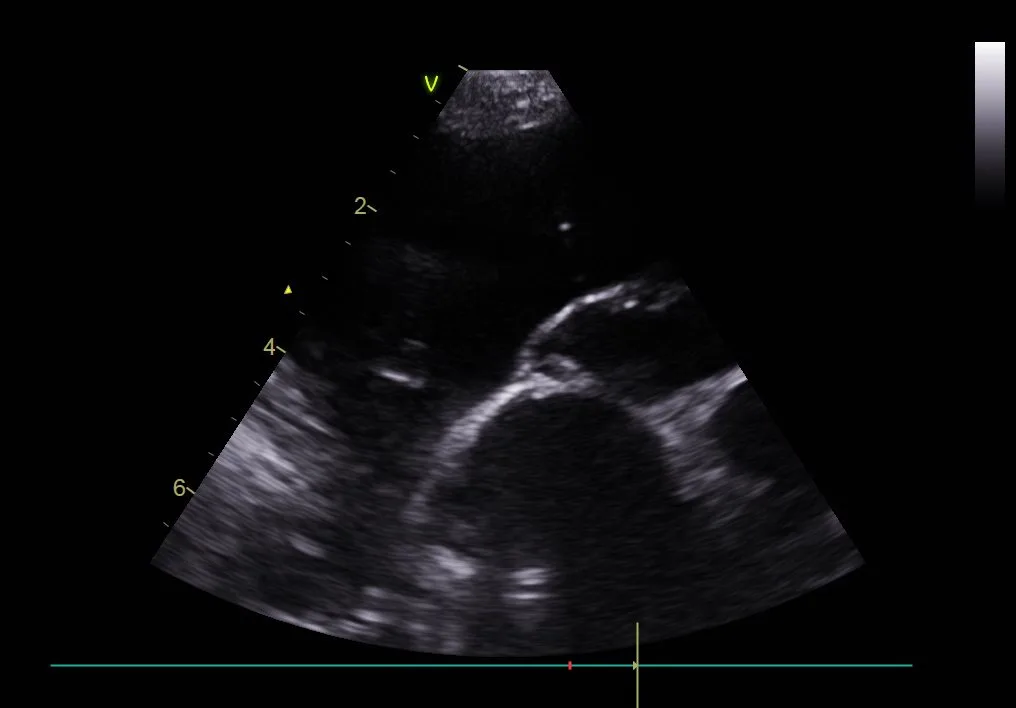

Thoracic ultrasound of the left side of the chest in a dog with marked pleural effusion